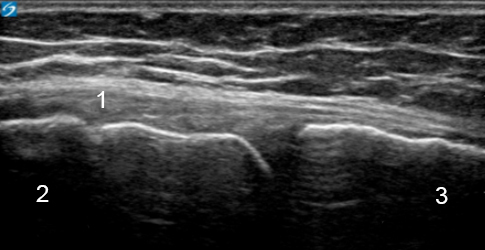

Knee Medial Joint Line Image

Medial Collateral Ligament (MCL)

Femur

Tibia